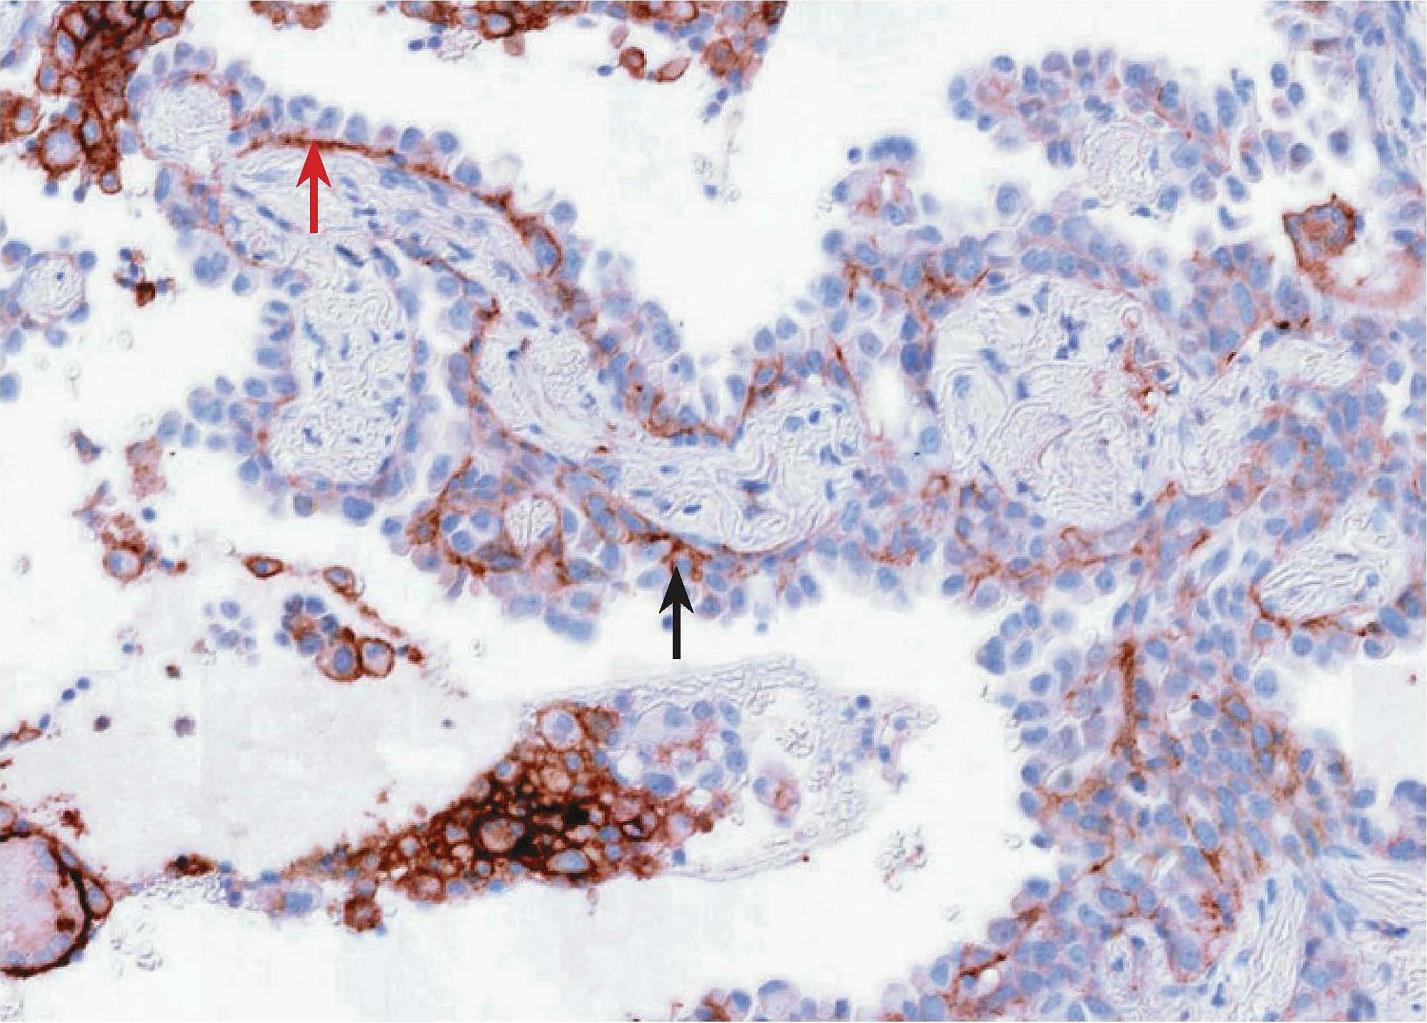

SP263克隆号检测平台及结果判读与22C3和28-8标准大致相同,判读结果以TC计算,不同的是若SP263仅有肿瘤细胞基底膜染色不能算作阳性,需基底膜及侧膜同时染色时才可判为阳性,根据肿瘤细胞PD-L1的表达分别为1%≤TC评分<5%、5%≤TC评分<10%、10%≤TC评分<50%、TC评分≥50%。图2-10和图2-11所示为肺浸润性腺癌HE染色图和PD-L1 (SP263)免疫组织化学染色图,图2-11显示肿瘤细胞基底膜及侧面均染色,应纳入PD-L1评估,TC评分≥50%。图2-12和图2-13所示为肺浸润性腺癌HE染色图和PD-L1 (SP263)免疫组织化学染色图,部分肿瘤基底膜及侧面均染色的肿瘤细胞(如黑色箭头所示),应纳入PD-L1百分比评估中,而染色的免疫细胞应排除PD-L1评估;部分肿瘤细胞仅基底膜染色,侧面未染色(如红色箭头所示),不应纳入阳性肿瘤细胞。不同TC评分的NSCLC PD-L1 (SP263)免疫组织化学染色结果如图2-14至图2-17所示。

图2-13 肺浸润性腺癌PD-L1 (SP263)免疫组织化学染色图(×400) [7]

注:部分肿瘤基底膜及侧面均染色的肿瘤细胞(如黑色箭头所示),应纳入PD-L1百分比评估中;部分肿瘤细胞仅基底膜染色,侧面未染色(如红色箭头所示),不应纳入阳性肿瘤细胞;染色的免疫细胞应排除PD-L1评估